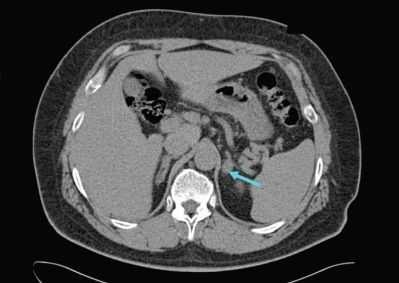

УЗИ надпочечников — низкочувствительный метод диагностики. Предпочтительнее проводить КТ: она помогает выявить как макро- и микроаденомы надпочечников, так и утолщения ножек надпочечников, гиперплазии и другие изменения [14] .

После подтверждения диагноза проводится компьютерная томография (КТ) органов брюшной полости для определения подтипа патологии. КТ проводится для определения причины гиперальдостеронизма - аденомы надпочечников, гиперплазии или карциномы (подозревается при обнаружении односторонней опухоли >4 см). Магнитно-резонансная томография (МРТ) не имеет преимуществ перед КТ, поэтому не рекомендуется в качестве стандартного метода обследования. Чувствительность КТ - 78%, специфичность - 75%.

Данные КТ надпочечников определяют дальнейшую тактику обследования и лечения. Например, если при КТ обнаружен односторонний гиподенсный узел (участок, отличающийся по плотности или цвету и четкими границами на изображении) и пациенту более 35 лет, следующий диагностический этап - исследование венозной крови надпочечников. Для уточнения того, где происходит перепроизводство альдостерона, проводят катетеризацию надпочечниковых вен и тест на венозную кровь надпочечников. Это золотой стандарт оценки латерализации первичного гиперальдостеронизма, с чувствительностью - 95% и специфичностью - 100%.